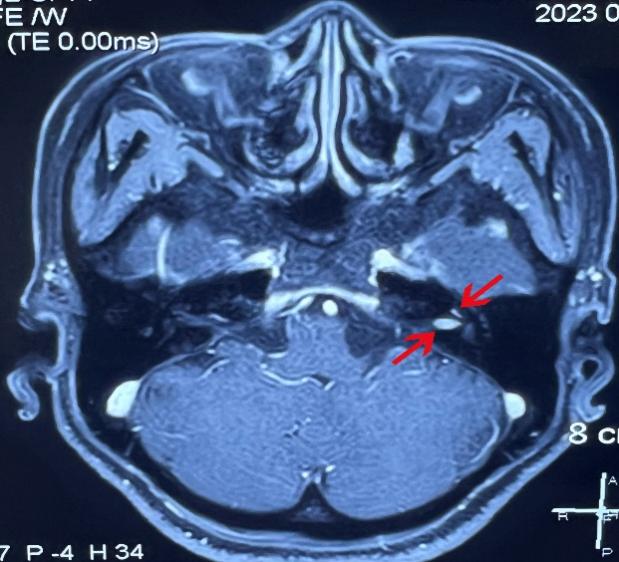

患者女,48岁,以“左耳听力下降伴间歇性眩晕1年”之主诉入院。纯音听阈示:左耳全聋;MRI发现左侧耳蜗-内听道占位,遂以听神经瘤收入我科。术前仔细阅片并与家属充分沟通,团队制定了详细手术方案,考虑到肿瘤侵及耳蜗底钻,且内听道部分6mm×3mm大小, 决定采用耳内镜下经过耳道、鼓岬入路切除肿瘤。但该患者颈静脉球高位,手术操作空间小、难度大,将耳后切开、显微镜下经迷路切除肿瘤做为备选方案。

2023年2月16日,宋正川副教授负责麻醉,手术室高明姬、张帅老师配合手术,吴宝俊、李阳副教授在耳内镜下完整切除骨性耳道皮肤及鼓膜,去除听锤骨、砧骨及镫骨,采用持续灌流-水下耳内镜技术完成外耳道扩大成形,显露颈内动脉、颈静脉球、面神经水平段和垂直段后,轮廓化内听道的前、下、后壁,直至内耳门,完全显露并切除耳蜗及内听道肿瘤,王军利、胡新成主治医师取腹部脂肪填塞术腔,关闭耳道。术后患者面神经功能完好,无脑脊液漏,术后7天安全出院。